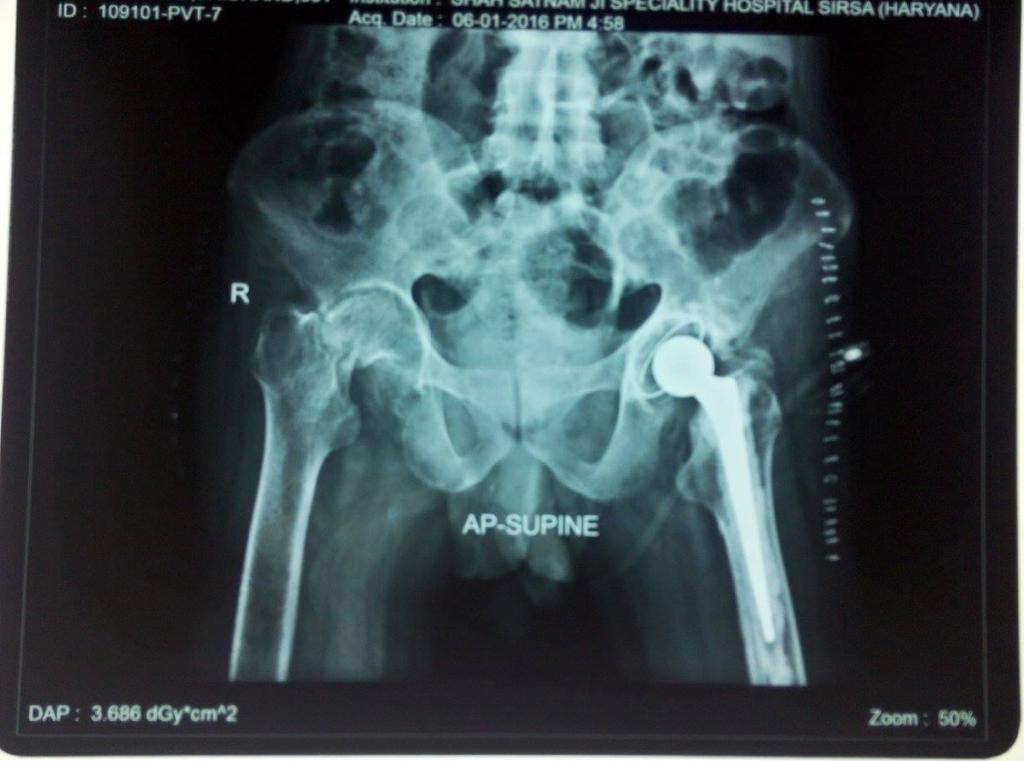

Hip replacement, medically termed hip arthroplasty, is a sophisticated surgical procedure meticulously designed to alleviate debilitating pain and restore functional independence in individuals afflicted by a damaged or severely arthritic hip joint. This transformative intervention becomes imperative when non-surgical remedies prove inadequate in mitigating pain and improving mobility. A comprehensive preoperative assessment is conducted, encompassing a meticulous review of the patient's medical history, a thorough physical examination, and the analysis of diagnostic imaging such as X-rays and MRIs. These evaluations serve to gauge both the patient's overall health and the extent of hip joint deterioration, helping the orthopedic surgeon determine the appropriateness of hip replacement.

In addition to the clinical evaluation, diagnostic imaging studies such as X-rays and MRIs are often performed. X-rays provide detailed images of the hip joint, allowing the surgeon to assess the extent of joint degeneration, bone damage, and alignment issues. MRIs offer a more comprehensive view of the soft tissues surrounding the hip joint, helping to identify conditions like cartilage damage or labral tears. Collectively, this comprehensive evaluation guides the surgeon in making an informed decision regarding the necessity and appropriateness of hip replacement surgery for the patient, taking into account their overall health and the severity of hip joint issues.

Implant placement is a crucial phase in the hip replacement surgery, where the artificial hip components are meticulously positioned and securely fixed within the joint. These components typically consist of the femoral stem, acetabular cup, and any associated parts, each carefully chosen to match the patient's unique needs and anatomy.

The surgeon's skill and precision are paramount during this step, as the proper alignment and placement of these components are essential for the success of the procedure. The femoral stem, typically made of metal, is inserted into the hollowed femur to provide stability and support. The acetabular cup, which can be composed of materials like ceramic or high-density polyethylene, is implanted in the hip socket to recreate a smooth, low-friction joint surface.

The choice of implant materials may vary based on the patient's specific needs and the surgeon's expertise. These materials are selected for their durability and compatibility with the patient's lifestyle, aiming for long-lasting pain relief and improved joint function.

Once the artificial components are securely in place, they mimic the natural hip joint's structure and function, offering patients the potential for renewed mobility and a significant reduction in pain. The success of implant placement significantly contributes to the overall effectiveness of hip replacement surgery.